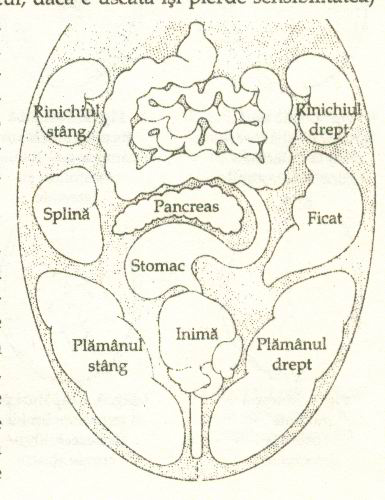

APARATUL DIGESTIV

APARATUL DIGESTIV Aparatul digestiv este constituit din totalitatea organelor care au ca functii principale digestia si absorbtia principiilor alimentari si eliminarea reziduurilor neasimilabile ale alimentelor ingerCiteste tot ... 1835 cuvinte

Dimensiune medie

+ cu poze |